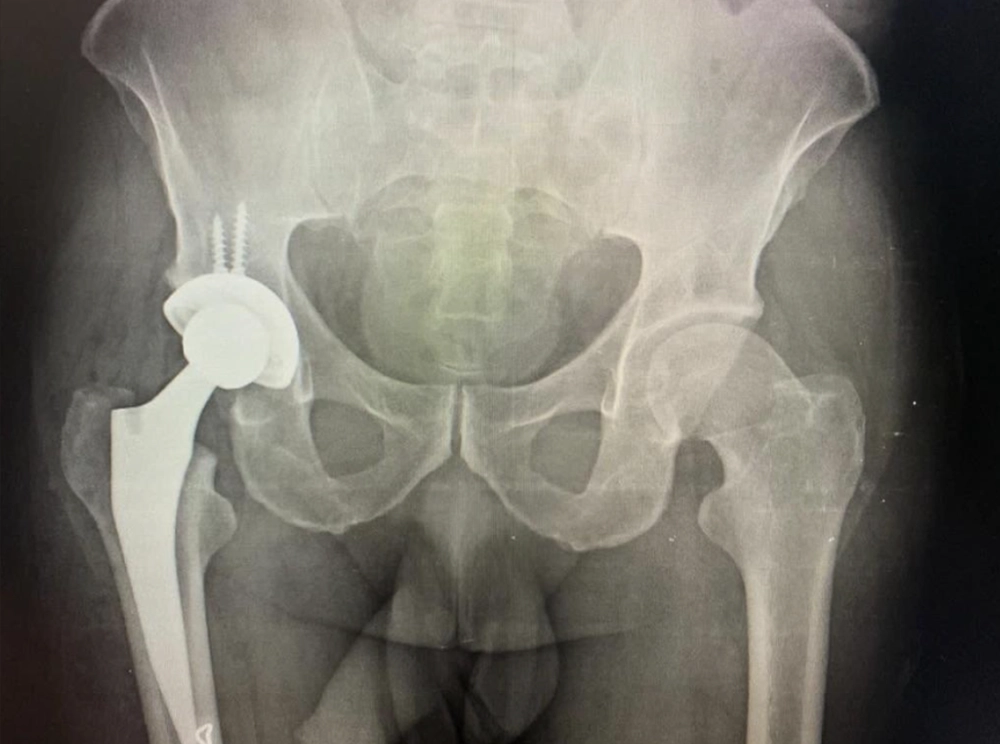

Exemplo de prótese total de quadril híbrida esquerda.

Existem no mercado diversos modelos de prótese de quadril para cirurgias primárias e revisões. Neste artigo, irei abordar os 3 principais tipos de próteses primárias realizadas: a não-cimentada (figura 3), a cimentada (figura 2) e as próteses híbridas onde geralmente o fêmur é cimentado e o acetábulo não cimentado (figura 4). A utilização de cada uma delas depende da experiência do cirurgião e da avaliação clínica de cada paciente.

Abaixo, você pode ver uma prótese híbrida onde o acetábulo foi realizado com um componente não-cimentado e no fêmur foi utilizado cimento: